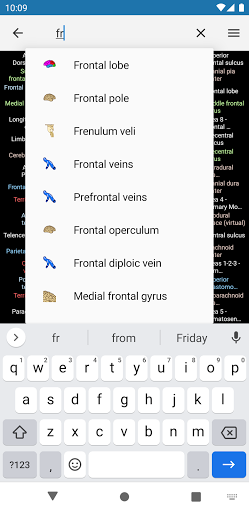

*Improving performance of anatomical structure search

*Improving performance of anatomical structure search

*Find your anatomical parts more easily thanks to the new, more intuitive and powerful search feature

-Implementation of search by patronyms.